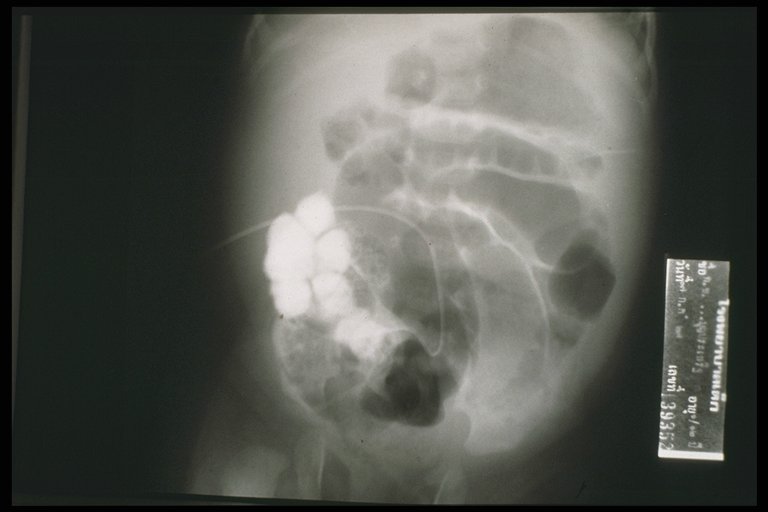

Fistulogram demonstrated the tract connected between the umbilicus and the intestine

At operation, a patent vitelline duct is demonstrated connected between the umbilicus and Meckel's diverticulum